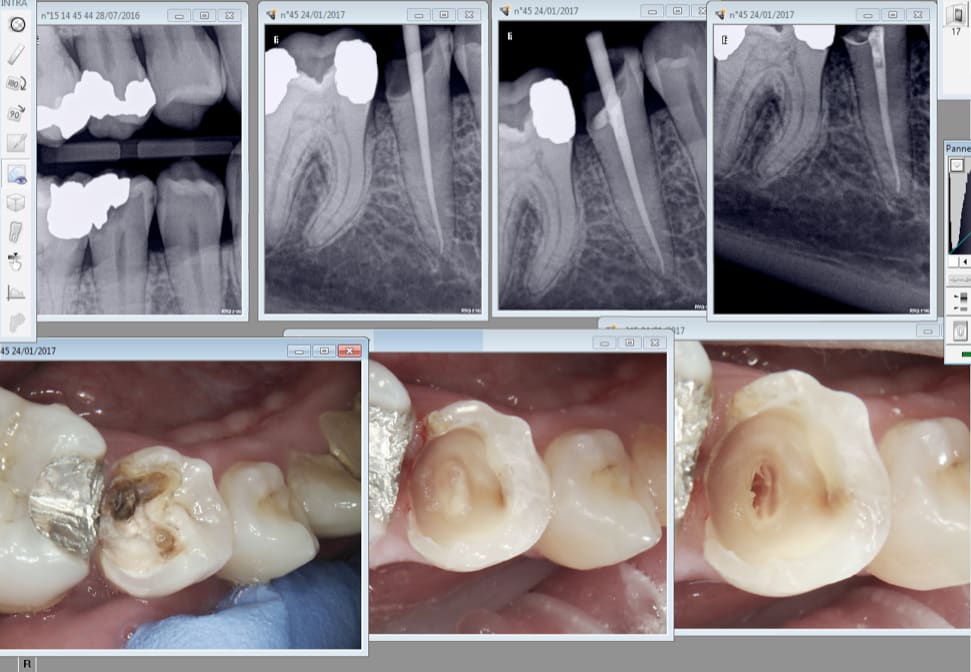

Bonjour à tous, je tiens avant tout à vous remercier pour vos suggestions et voici une radio.

ps: je tiens à préciser que la 42 présentait déjà une obturation canalaire incomplète (comme vous pouvez remarquer).

Pour le cas présenté, il s'agit en effet d'un problème d'axe. Car la lumière canalaire est très nettement visible, il ne devrait donc pas y avoir de probleme. Comme le suggère Chico29, descendre la hauteur coronaire ça limitera le risque de partir en perf et ça amènera une meilleure visibilité.

L'abrasion ne m'a pas l'air si sévère que ça sur la radio...

Quoi qu'il en soit, si le bloc incisivo-canin avait besoin d'être couronné, j'aurais gardé ces dents "vivantes" (seulement retraitement de la 42), car :

- le parenchyme pulpaire est rétracté et à bonne distance,

- la hauteur coronaire à l'air suffisante pour avoir une bonne rétention/stabilisation des couronnes,

- les incisives mandibulaires sont souvent difficiles à dévitalisées, et présentent souvent deux canaux...